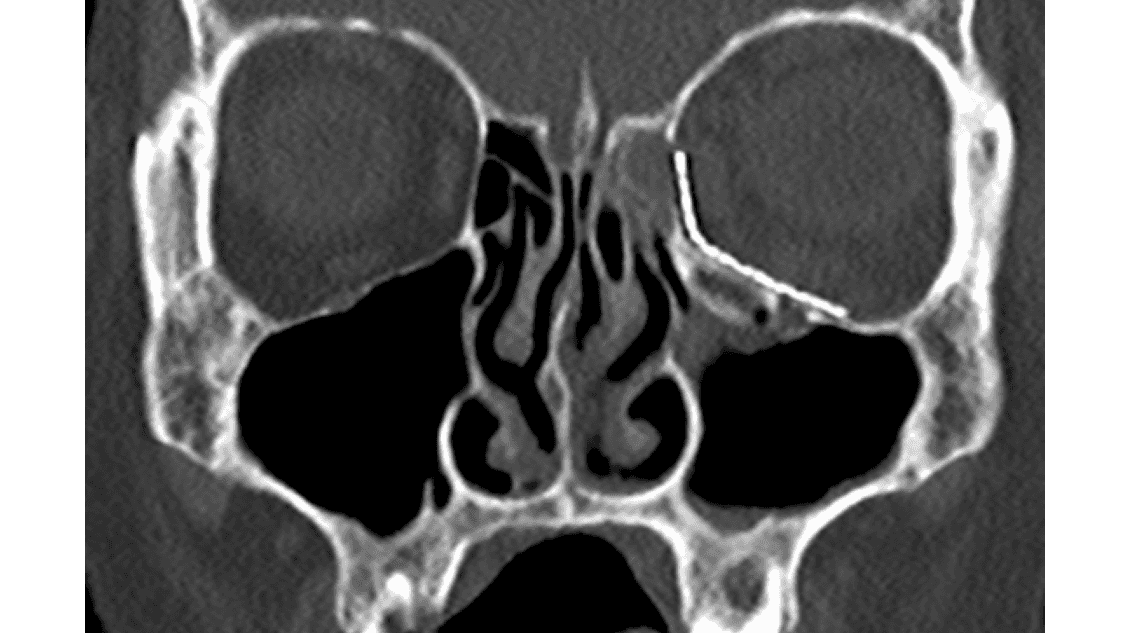

Hjertet er en hormonfabrik